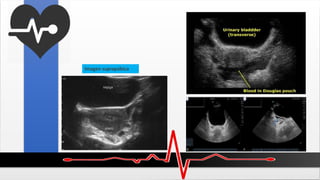

FAST (evaluación con ultrasonido focalizada en trauma)

Incluye las siguientes imágenes ecográficas:

Imagen pericárdica:

Imagen del cuadrante superior derecho (fosa hepatorrenal)

Estudios de Imagen

Imagen del cuadrante superior izquierdo (fosa esplenorrenal)

Imagen suprapúbica